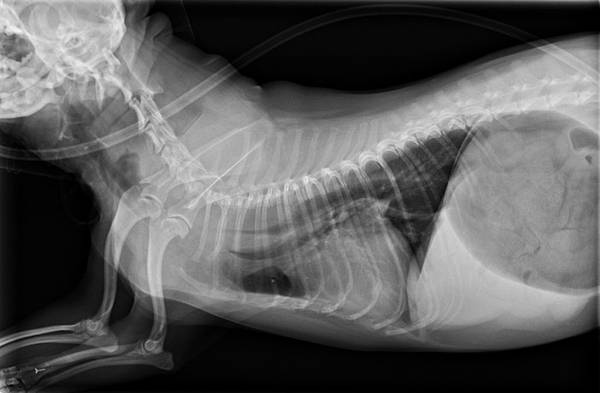

手術前

經過醫療團隊緊急安裝氣管支架後

恢復非常好

未命名1.jpg

手術完